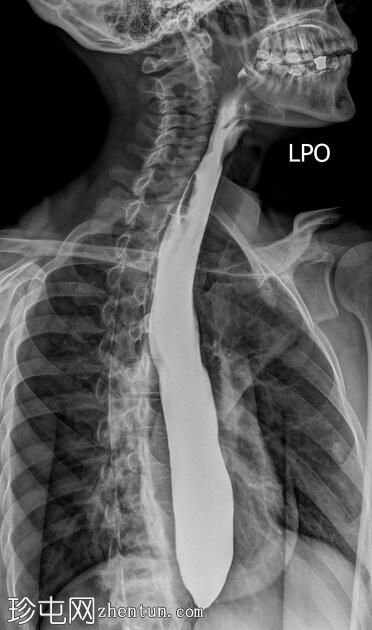

斜位

食管扩张,远端平滑狭窄并呈锥形(鸟嘴状),符合贲门失弛症的特征性表现

食管黏膜形态正常,无异常或溃疡

未见食管裂孔疝

钡餐检查显示食管扩张,远端狭窄并呈锥形,形成符合贲门失弛症特征的鸟嘴状外观。